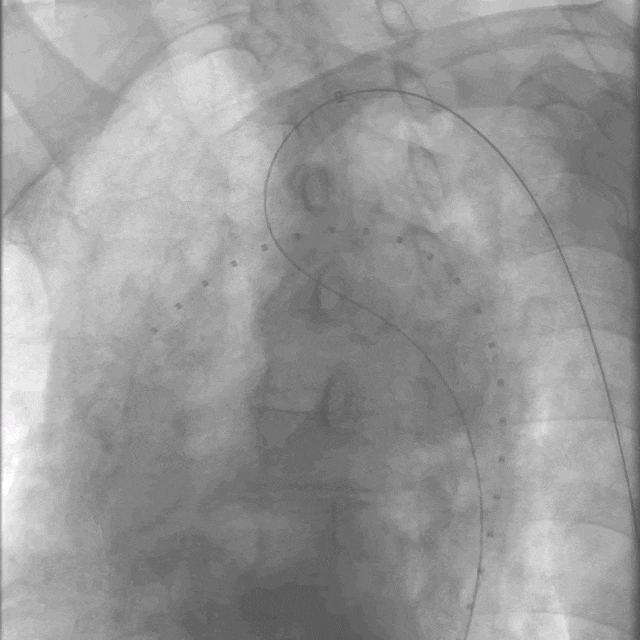

01.  患者取平卧位,常规消毒铺单,按照Seldinger方法穿刺右侧股总动脉及左侧肱动脉,于左侧肱动脉引入猪尾导管用于术中标记,于右侧股动脉预置两把缝合器,引入泥鳅导丝及Pigtail导管至升主动脉,造影提示胸主动脉溃疡。

泥鳅导丝怎么用曲乐丰教授团队:0.018"和0.035"普通泥鳅导丝行胸主动脉弓上分支原位开窗的病例分享_https://www.jmylbn.com_新闻资讯_第8张

术前造影